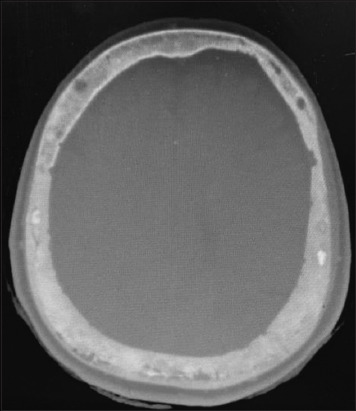

Background and aim: Paget's disease of the bone refers to a chronic cumulative disorder characterized by enhanced osteoclastic function followed by a secondary surge in osteoblastic activity. The condition can manifest as a polyostotic or monostotic bone disease with most patients having an asymptomatic presentation, although some may complain of pain localized to the affected bone while others express symptoms of nerve compression. A pagetic bone is predisposed to develop pathological fractures, bony deformities, and a rare yet detrimental transformation into osteosarcoma. Detection is often accidental when performing radiographic tests for other indications or when elevated blood levels of alkaline phosphatase (ALP) are detected. Treatment with third-generation bisphosphonates is helpful in preventing further bone resorption and, additionally, reduces bony pains that are believed to be caused by excessive metabolic activity. Here, we present a case of a middle-aged asymptomatic female with elevated serum ALP levels up to 1537 IU/L (reference range 40-150 U/L) during her pre-operative evaluation for elective cholecystectomy.99m Tc-methylene diphosphonate bone scintigraphy revealed diffuse uptake in the skull and, hence, was diagnosed as a case of isolated Paget's disease of the skull.

Relevance for patients: The rarity of this disease in Southeast-Asians, its uncontrived detection, and the isolated skull involvement, imparts high clinical relevance on this case. Early detection and management of this disease can help prevent the development of life-threatening complications in affected patients, hence decreasing the morbidity.